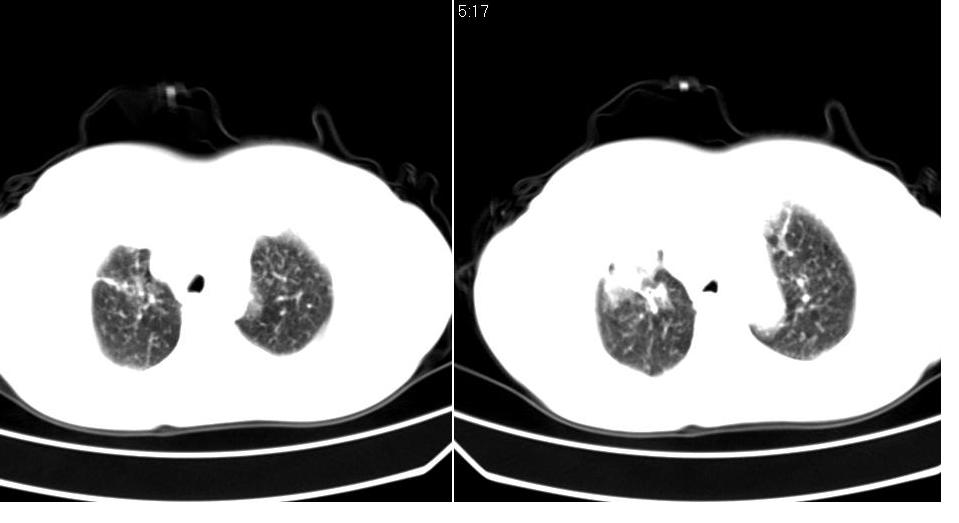

标题: CT16839:胸部CT平扫

女 50岁,在其他医院确诊肺癌.

肺癌并肺及纵隔转移

支持 右肺上叶肺癌并两肺及纵隔转移。